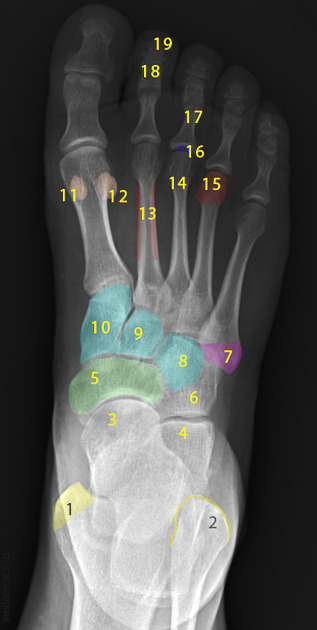

Two unlabeled illustrated images, figures 1 and 2, of the foot and one unlabeled x-ray image, figure 3, were selected. Each image was inputted into ChatGPT Version 4o and the model was prompted to identify the bones depicted in each image using the following prompt.

Prompt 2: ‘Identify the structures labeled in this image’

Two prompts were entered into ChatGPT (Prompt 1: “Make me a picture of human foot with the bones labeled”, Prompt 2: “Identify the structures labeled in this image”). Results of prompt 1, seen in figure 4, are that the generated image was detailed and visually appealing, correctly displaying a foot with visible bones as requested. However, the labeling is entirely inaccurate, with misspelled anatomical terms, misplaced labels, and several missing bones, including the phalanges of the 4th toe. The result of prompt 2 for the first illustrated image is 27% accurate with 3 of 11 bones accurately identified as shown in table 1. The result of prompt 2 for the second illustrated image is 57% accurate with 4 of 7 bones accurately identified as shown in table 2. The result of prompt 2 for the x-ray image is 0% accurate with 0 of 19 structures accurately identified as shown in table 3.

Out of 19 labels, 19 were identified correctly, resulting in an accuracy of 0%.

The output from ChatGPT v4o of prompt 1 "‘Make me a picture of human foot with the bones labeled’ demonstrates a visually appealing and detailed depiction of a human foot with visible bones. However, the labeling is inaccurate, with anatomical terms misspelled, labels misplaced, and several key bones, such as the phalanges of the 4th toe, completely missing. Prompt 2 reveals varying accuracy between the 3 images used: 27% for the first illustrated image, 57% for the second illustrated image, and 0% accuracy for the x-ray image.